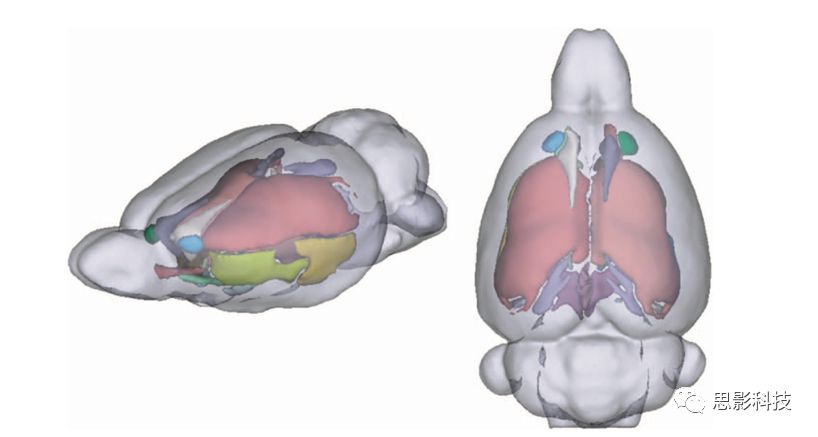

三、sMRI數(shù)據(jù)處理業(yè)務(wù)

1、基于體素的形態(tài)學(xué)分析(VBM)

借助FSL/VBM8等工具包對T1像進(jìn)行分割、配準(zhǔn)并計(jì)算灰白質(zhì)體積密度。

灰白質(zhì)分析圖例